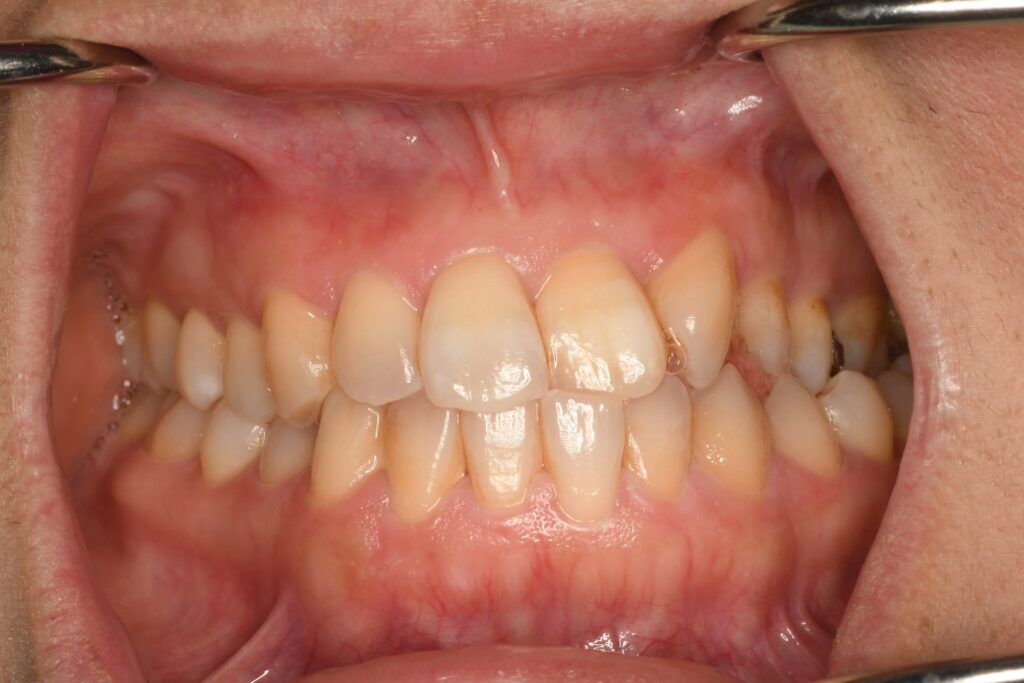

今回は左上側切歯(中央の歯から1本隣の歯)が先天欠損(生まれた時からない)なので、ズレて噛み合わせが崩れてしまったようです。あまり気になっていなかったようですが、当院で定期検診を繰り返すうちに歯並びを整えたいという思いが強まって矯正治療をすることになりました。このような時もですが、どんな状態でも精密検査は欠かせません。簡単、難しいに関わらず状況を把握することが大事です。

もともと1本ない状態を見た目も含めてどのように整えるのか?今回の焦点はこの1点です。数パターン提示させてもらって、今回は歯を抜かないし、もともとない1本のところに隙間を作るらずに歯並びを整える治療計画にしました。